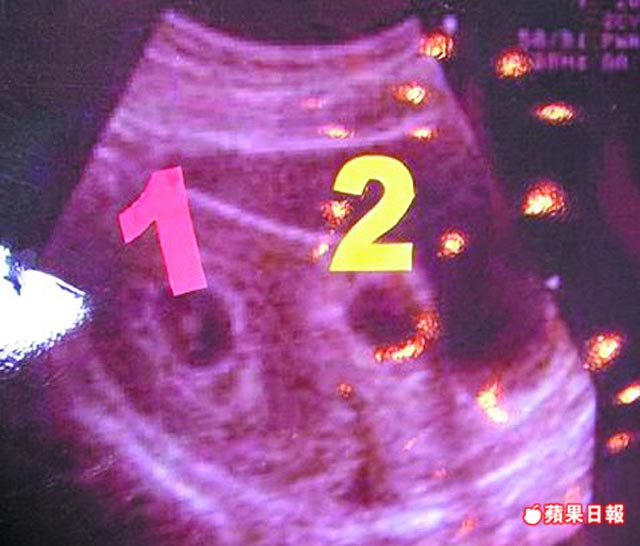

53歲嬤產雙胞孫抱「小阿姨」 「上天給我最好母親節禮物」 去年在博元婦產科院長蔡鋒博醫師協助下進行人工受孕,還一次懷了三胞胎,後來經過減胎,年初產下一對雙胞胎姊妹。